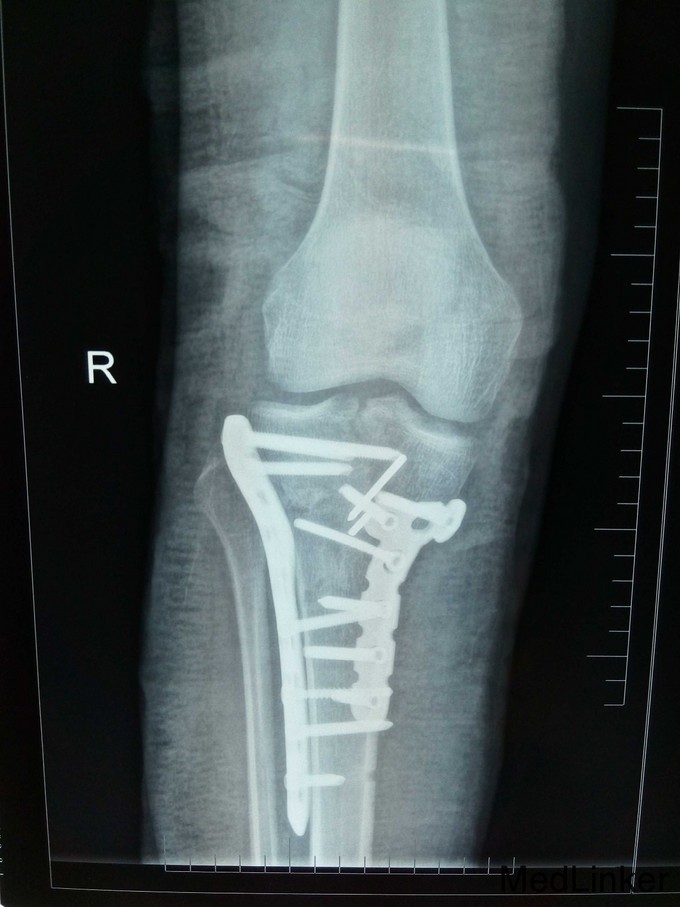

右胫骨平台粉碎性骨折(内外髁骨折) 入院后予跟骨骨牵引,一周后硬外麻下行胫骨平台骨折切开复位内固定术,术后伤口拆线痊愈出院。

胫骨平台骨折分6型,患者内外髁骨折,属第6型,手术采用内外侧切口钢板固定植骨术,该患者胫骨结节撕脱性骨折,故术中加用两条克氏针(螺丝无把持力)。请各位前辈赐教。